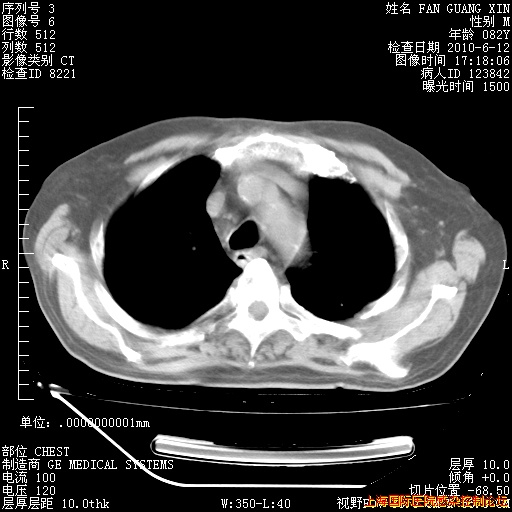

补发6月12日肺部CT肺窗

6月12日肺窗

6月12日纵膈窗